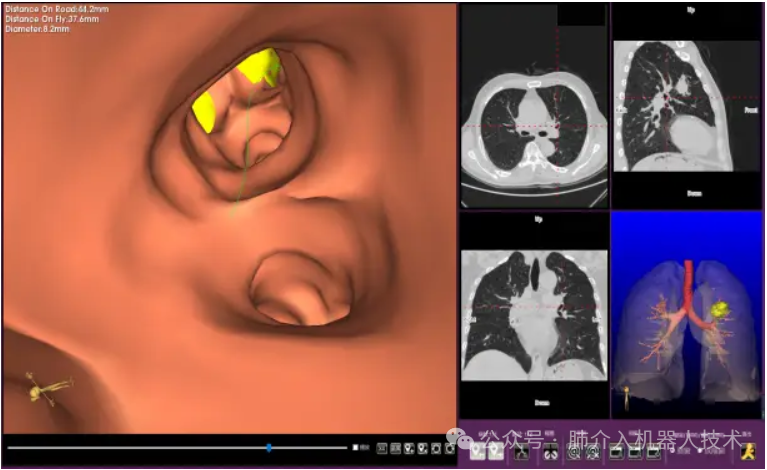

03、奧泰康助力肺部穿刺手術(shù)導(dǎo)航系統(tǒng)獲證

2024年1月31日,經(jīng)國家藥品監(jiān)督管理局公示,蘇州朗開醫(yī)療技術(shù)有限公司自主研發(fā)的肺部穿刺手術(shù)導(dǎo)航系統(tǒng)(國械注準(zhǔn)20243010222)獲得NMPA批準(zhǔn)上市,奧泰康助力本項(xiàng)目注冊申報(bào)服務(wù),系2024年奧泰康助力獲得的首張三類醫(yī)療器械注冊證。